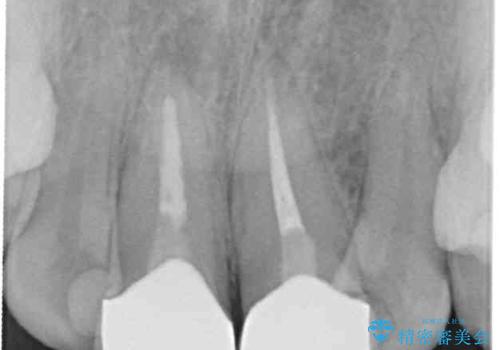

レントゲン写真より、歯根の炎症が認められず、土台もしっかりと植立されていたため、仮歯に置き換えた後にオールセラミッククラウンにて補綴することとしました。